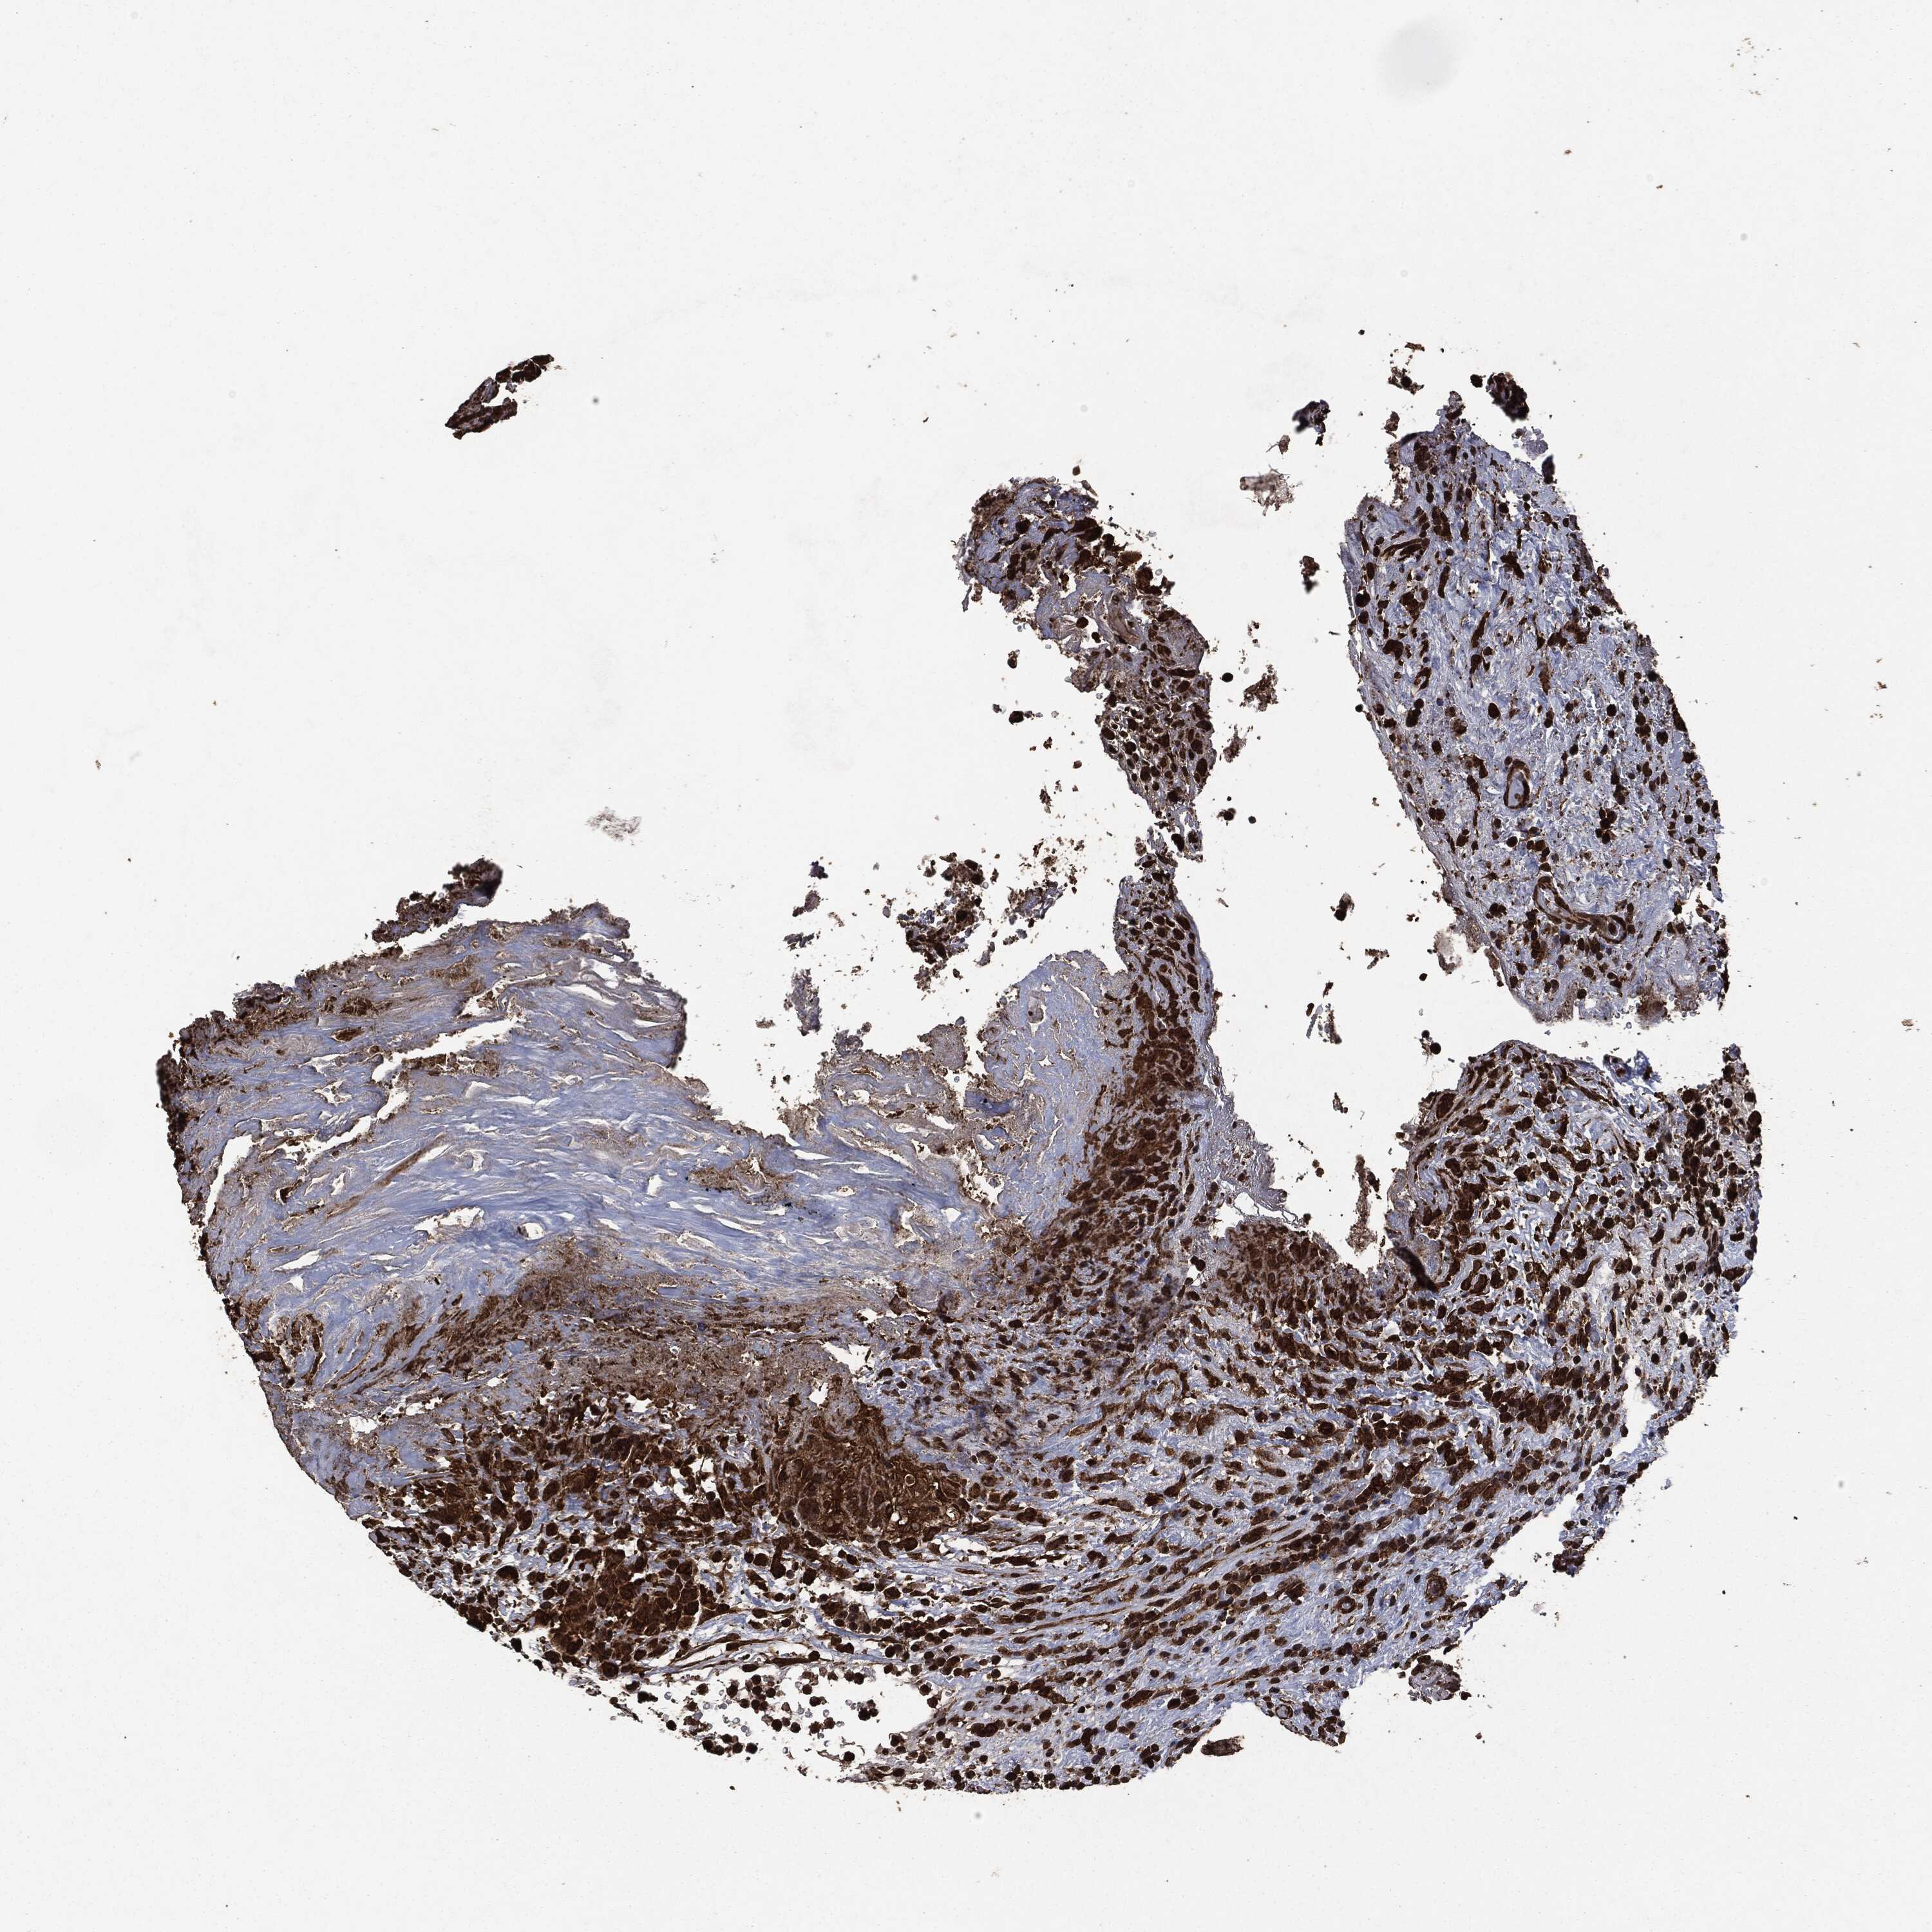

UROTHELIAL CANCER - Protein expressioni

A mouse-over function shows sample information and annotation data. Click on an image to view it in a full screen mode. Samples can be filtered based on level of antibody staining by selecting one or several of the following categories: high, medium, low and not detected. The assay and annotation is described here.

Note that samples used for immunohistochemistry by the Human Protein Atlas do not correspond to samples in the TCGA dataset.

Antibody stainingi

Antibody staining in the annotated cell types in the current human tissue is reported as not detected, low, medium, or high, based on conventional immunohistochemistry profiling in selected tissues. This score is based on the combination of the staining intensity and fraction of stained cells.

Each image is clickable and will lead to virtual microscopy that enables deeper exploration of all samples and also displays staining intensity scores, fraction scores and subcellular localization as well as patient and tissue information for each sample.

CAB080330

CAB080331

CAB080332

Urothelial carcinoma, High grade

Urothelial carcinoma, NOS

Urothelial carcinoma, Low grade

Adenocarcinoma, NOS